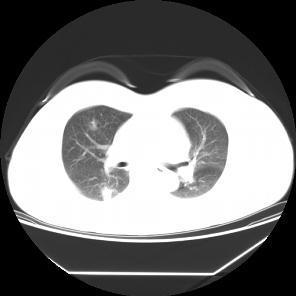

患者,女,57岁,因“右肺占位”于2015-09-17 15:08入院。 患者缘2月前体检无意发现右肺占位,伴随症状:无咳嗽、咳痰、无胸闷、胸痛、气短,无头晕、视物旋转,无恶心、呕吐,无腹痛、腹泻,无尿急、尿频、尿痛,2015-7-1 CT示:1.右肺上叶前段及下叶背段结节伴实变,右肺下叶结节见支气管气相征,考虑炎性病变可能,建议治疗后复查除外肿瘤性病变;双肺多发炎症;2.双侧胸膜肥厚;肺动脉增宽,提示肺动脉高压;3.肝左外叶小囊肿;4.甲状腺双叶增大,考虑为甲状腺肿,请结合临床。2015-9-2复查CT示:1.右肺上叶前段结节较前片无明显变化;右肺下叶背段结节较前片增大,建议进一步检查除外肿瘤性病变;双肺多发炎症较前片吸收;2.双侧胸膜肥厚;肺动脉增宽;3.肝左外叶小囊肿;4.甲状腺肿大,同前片。以“右肺占位”收住院,自发病以来,食欲减低,体重无明显下降,大小便无异常。

诊断为右肺上叶前段,下叶背段高分化腺癌,T4N0M0(IIIA)期 行胸腔镜手术楔形切除术,术后测EGFR阳性,给予分子靶向药物埃克替尼治疗

患者无任何症状,体检发现肺部小结节影,观察2月,未见缩小,似有轻度增大,入院后经CT引导下肺穿刺活检提示高分化腺癌,行手术治疗。 周围型肺癌早期影像学表现为孤立的肺内结节或肿块,通常有分叶征,毛刺征,空泡征,支气管充气征,坏死液化或空洞形成。此患者仅表现为淡薄的渗出影,小结节影,观察2月没有变化后,经穿刺证实肺癌,因此对肺部小结节影,斑片影,不吸收,无钙化的要特别注意肿瘤可能。